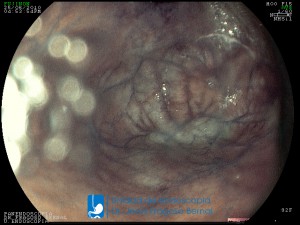

La Unidad de Endoscopía fue creada en 2002 por el Dr. Jesús Fragoso Bernal, es pionera en el estado por la utilización de la tecnología más avanzada, que nos permite ofrecer servicios integrales de diagnóstico y tratamiento para las enfermedades del aparato digestivo.